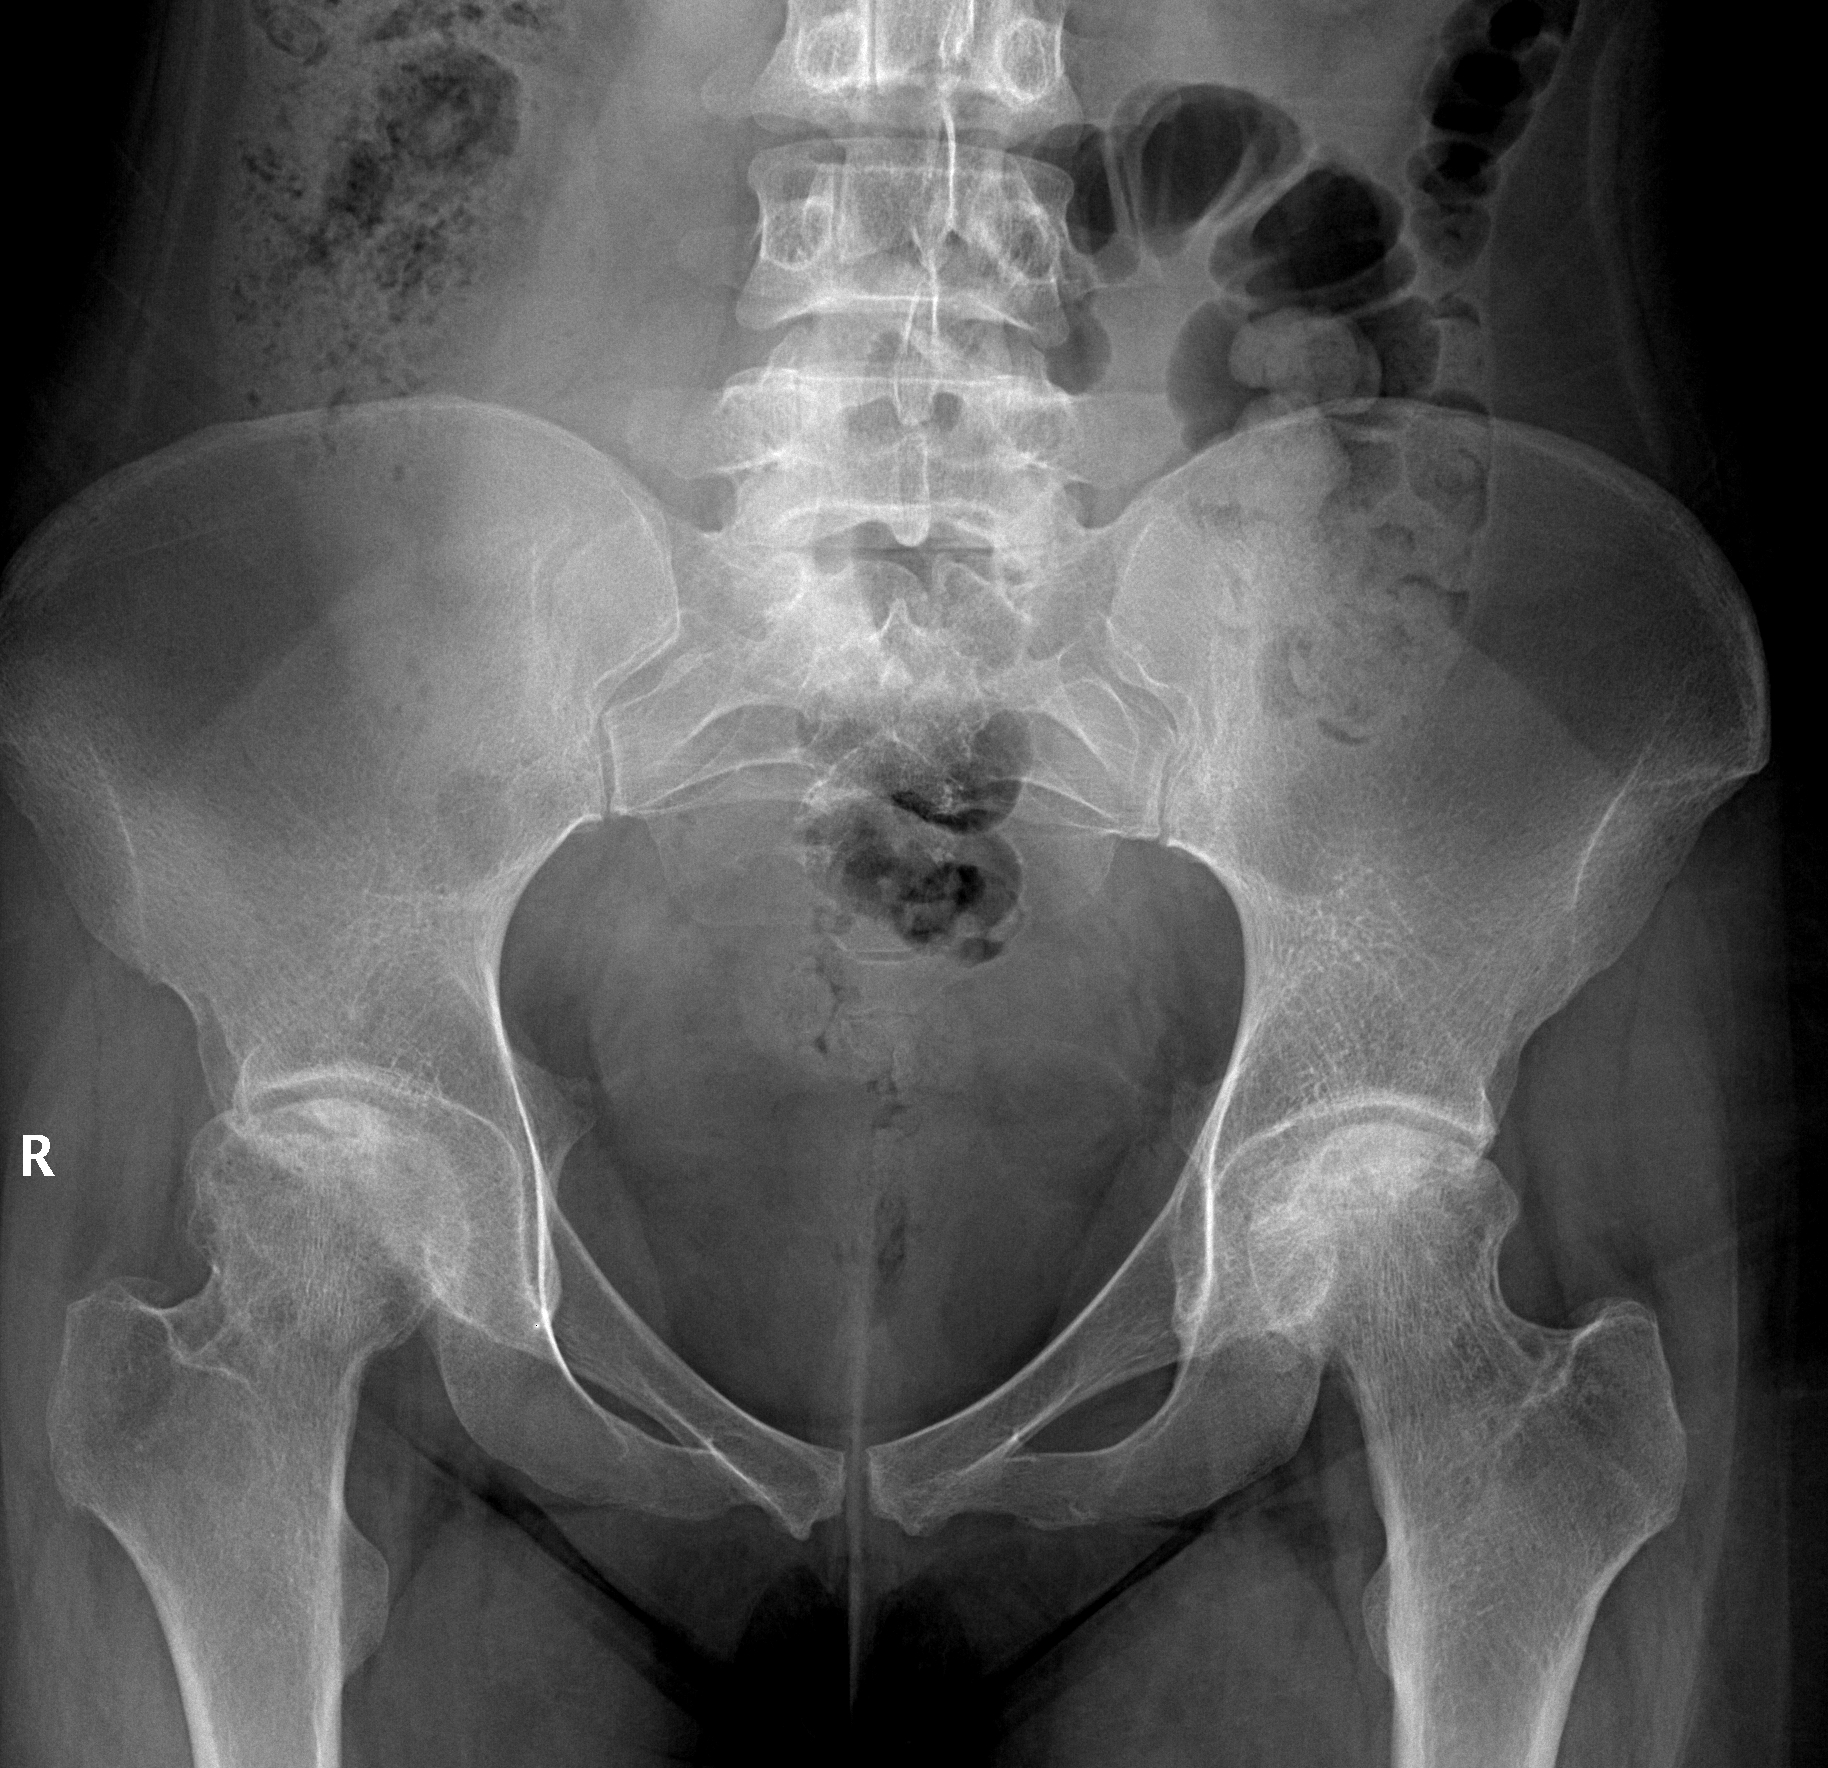

Welche Verdachtsdiagnose stellen Sie basierend auf diesen Röntgenbild einer 50-jährigen Patienten mit bilateralen Hüftschmerzen unter Steroid-Therapie?